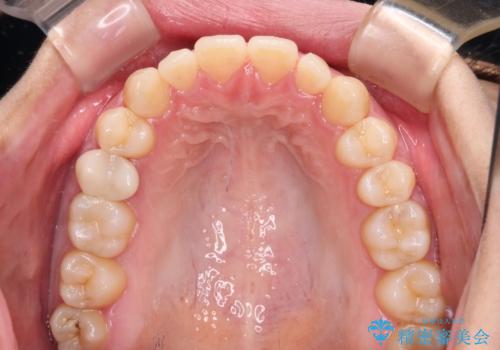

隙間だらけの歯列 インビザラインで改善

舌癖を改善するためのトレーニングを行いながら、インビザラインにより上下の前歯の隙間を閉じていくこととしました。

空隙歯列(すきっ歯)は、舌の突出癖をある程度改善できたとしても、後戻りにより隙間が開きやすいと言われています。

裏側から細いワイヤーで保定するとともに、睡眠時のマウスピース装着を徹底していただくことで、後戻りを最小限にとどめます。